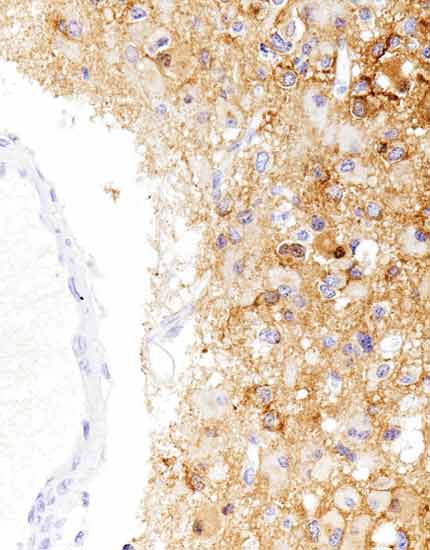

产品名称:Pepsinogen I

产品编号:MAB-1046

阳性部位:细胞质

图片描述:

胃底腺型胃癌,Pepsinogen I染色,细胞质阳性